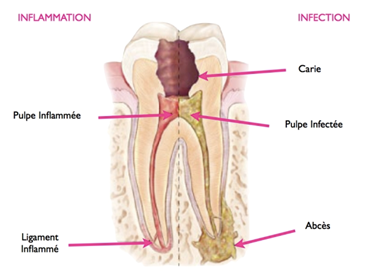

Appelé également «traitement canalaire», «pulpectomie» ou encore «dévitalisation», l'endodontie est l’un des soins dentaires les plus pratiqués dans un cabinet dentaire.Ce soin est obligatoire quand une infection a gagné les canaux suite à une carie non soignée. La pulpe doit être nettoyée et désinfectée afin d'éviter une récidive sous une couronne. Ce soin dentaire est réalisé en plusieurs étapes : Le praticien élimine les tissus encore vivants à l'aide de limes adaptées puis injecte de la chlorhexidine. Il obture ensuite les canaux concernés Une endodontie se fait sous anesthésie locale. Elle est plus ou moins longue à réaliser selon que ce soin dentaire vise une incisive (1 canal), une prémolaire (2 canaux) ou une molaire (3 canaux).

Aux premiers stades de développement de la carie dentaire, les symptômes sont plutôt rares. Ce n’est que lorsque la carie dentaire progresse que des symptômes apparaissent : sensibilité, initialement au froid puis au chaud et à la pression et douleur dentaire. En cas d’atteinte de la pulpe dentaire (nerf), la dent peut mourir et être à l’origine d’un abcès dentaire.